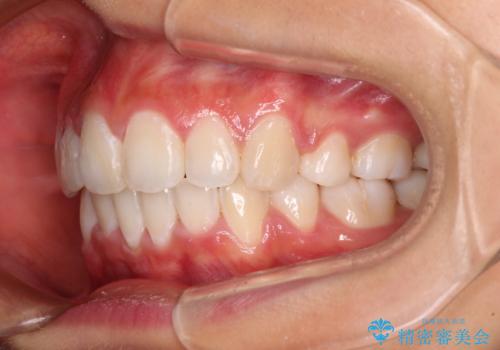

口元の突出感を改善 2年弱での抜歯矯正

- 出っ歯とデコボコを気にして来院された患者様です。

口元の突出感を改善するため、上下左右第一小臼歯4本の抜歯を行い、ワイヤー装置による矯正治療を行うこととしました。

治療前の上下正中はずれていましたが、骨格的な上下左右差はあまり認められなかったため、正中を揃えて治療を終えることができました。

1年半ほどで治療を終えることができるとは我々も想像しておらず、患者様には大変満足していただきました。